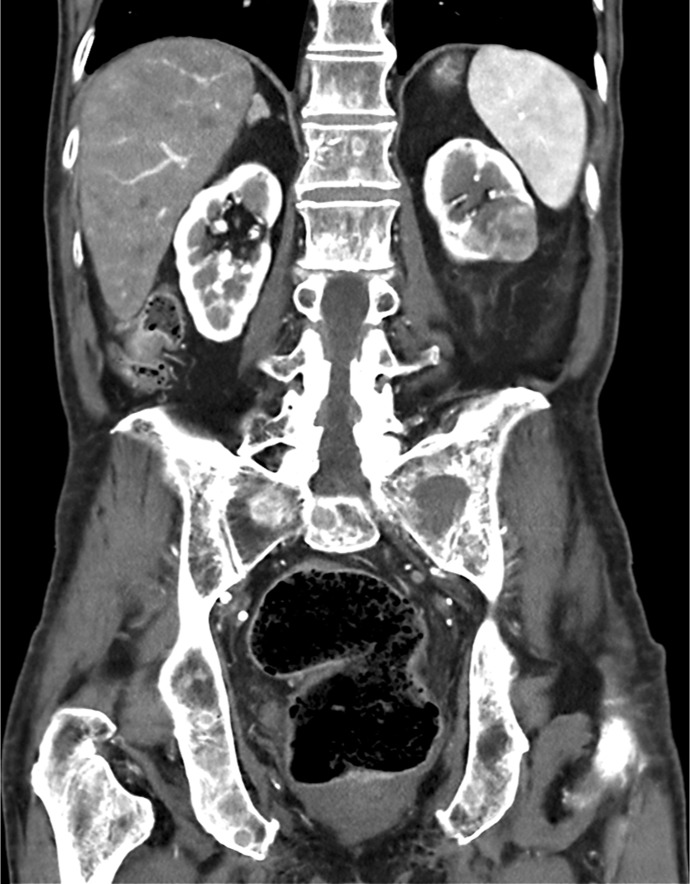

Case presentation: An 81-year-old male with a history of age-related macular degeneration presented with acute onset of pain and restricted movement in his left eye. Computed tomography imaging revealed an osteolytic lesion in the left sphenoid bone, causing reactive myositis. Further systemic evaluation identified a left renal mass with evidence of pulmonary and skeletal metastases. A core needle biopsy confirmed the diagnosis of metastatic renal cell carcinoma. Given the advanced disease stage, the patient was managed with palliative treatment. Despite medical interventions, he succumbed to the disease 6 months after symptom onset.